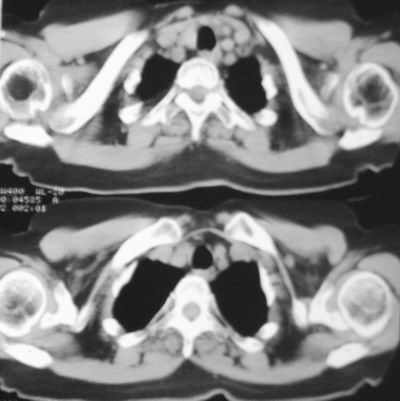

患者,女,64岁,4年前左腮腺"多形性"腺瘤手术治疗史.现复查胸部ct见左下肺块状影,该影与原左腮腺手术是否有联系?

术前(4年前)ct报告书

表现:左腮腺增大,于颞下见一约2.6x1.6x2.0cm混杂密度块影,边界较模糊,增强前后ct值约5-32hu、7-67hu,邻近骨质及软组织未见明确破坏征象,咽旁间隙尚存,周围未见肿大淋巴结。

诊断:左侧腮腺增大,抗炎治疗后复查,请结合临床分析。

术前(4年前)胸部dr报告书

表现:胸廓左右对称,气管居中,两肺野纹理增多,左下肺见一高密度影,周围见纤维条索影,心影及肺门无增大,双肋膈角锐利,横膈未见异常。

诊断:建议ct检查、随访。

本次复查胸部ct